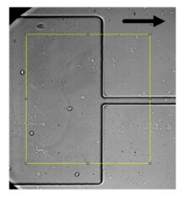

Figure 2. Microfluidic devices to assess of motions and deformations of red blood cells (RBCs) from healthy donors and pathological patients, e.g., chronic renal disease and diabetes mellitus [50]. ROI—Region of interest; PDMS—Polydimethylsiloxane; WBCs—White blood cells; RBCs—Red blood cells.

As previously mentioned, malaria and diabetes are some of the several existent RBCs-related diseases that can promote significant alterations in the RBC deformability. For this reason, the deformability of RBCs has been extensively studied and, recently, microfluidic devices have become the preferred method to measure the deformation of blood cells due to their dimensional match with biological cells and the aforementioned advantages. A summary of the main features of several cell deformability studies performed in microfluidic devices is presented in Table 1. Lima’s and Lee’s research group have applied a hyperbolic shaped microchannel [50,51,73,74] to study the RBCs deformability demonstrating that single RBCs deformability analysis can provide more precise and detailed information about blood disorders. In a more recent study performed by Faustino et al., 2018 [23], based in the work of Pinho et al., 2013 [26] and Rodrigues et al., 2015 [27], they have combined several passive sorting methods. In this work, separation by the biomechanical cells properties, hydrodynamic phenomena and hemodynamic cells behavior were fully integrated in a single microfluidic system to achieve single RBC visualizations and respective mechanical properties of cells (i.e., deformability) analysis. In addition, the separation efficiency was quantified by a spectrophotometric method. Briefly, this integrated microfluidic platform comprises several stages of cross-flow filtration barriers with different gaps and nine different outlets in order to access partial separation of RBCs and consequentially their deformability. At each outlet, a sequence of hyperbolic channels for cells visualization and deformability assessments is presented, which simultaneously can assess RBCs, WBCs, and other kinds of cells. The cells’ deformability was obtained, due to the use of hyperbolic-shaped contractions, which generate constant strain-rates that makes this tool a promising strategy for measuring RBCs deformability under a well-controlled microenvironment. More detailed information about this device can be found at the work performed by Faustino et al., 2018 [23]. Another example, showing the potential of this microfluidic approach, was the work performed by Rodrigues et al., 2016 [73]. In this study, this methodology was used to evaluate the impact of nanoparticles on human RBCs. The applied microfluidic tool has shown that a small amount of nanoparticles can affect the RBC deformability, where other hemocompatibility tests (such as the hemolysis analysis) did not show any influence. Hence, this study has shown that this microfluidic tool has a higher sensitivity to detect small changes of RBC deformability, task not possible by using conventional hemocompatibility methods. This microfluidic tool is currently being applied in novel studies including pathological flow studies and hemocompatibility tests (Figure 2).